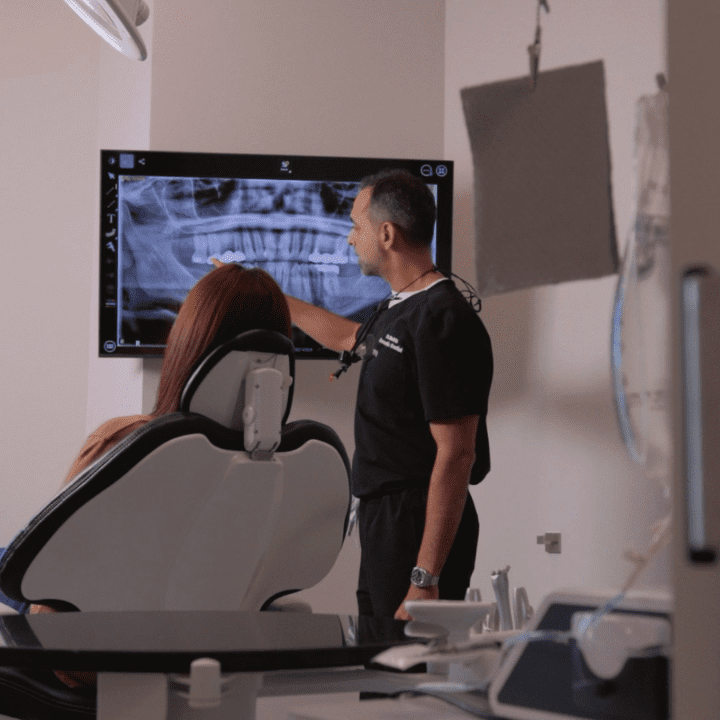

Implant Dentist Dr. Akhil Mehta & Patient

Top Rated Dental Implant Team Near Phoenix, AZ

Board Certified Cosmetic Dentist Dr. Akhil Mehta, Board Certified Oral Surgeon Dr. Amogh Velangi, and In-House Anesthesiologist Dr. Aaron Roberts Deliver Comprehensive Affordable Smile Transformations All In One Convenient Location.